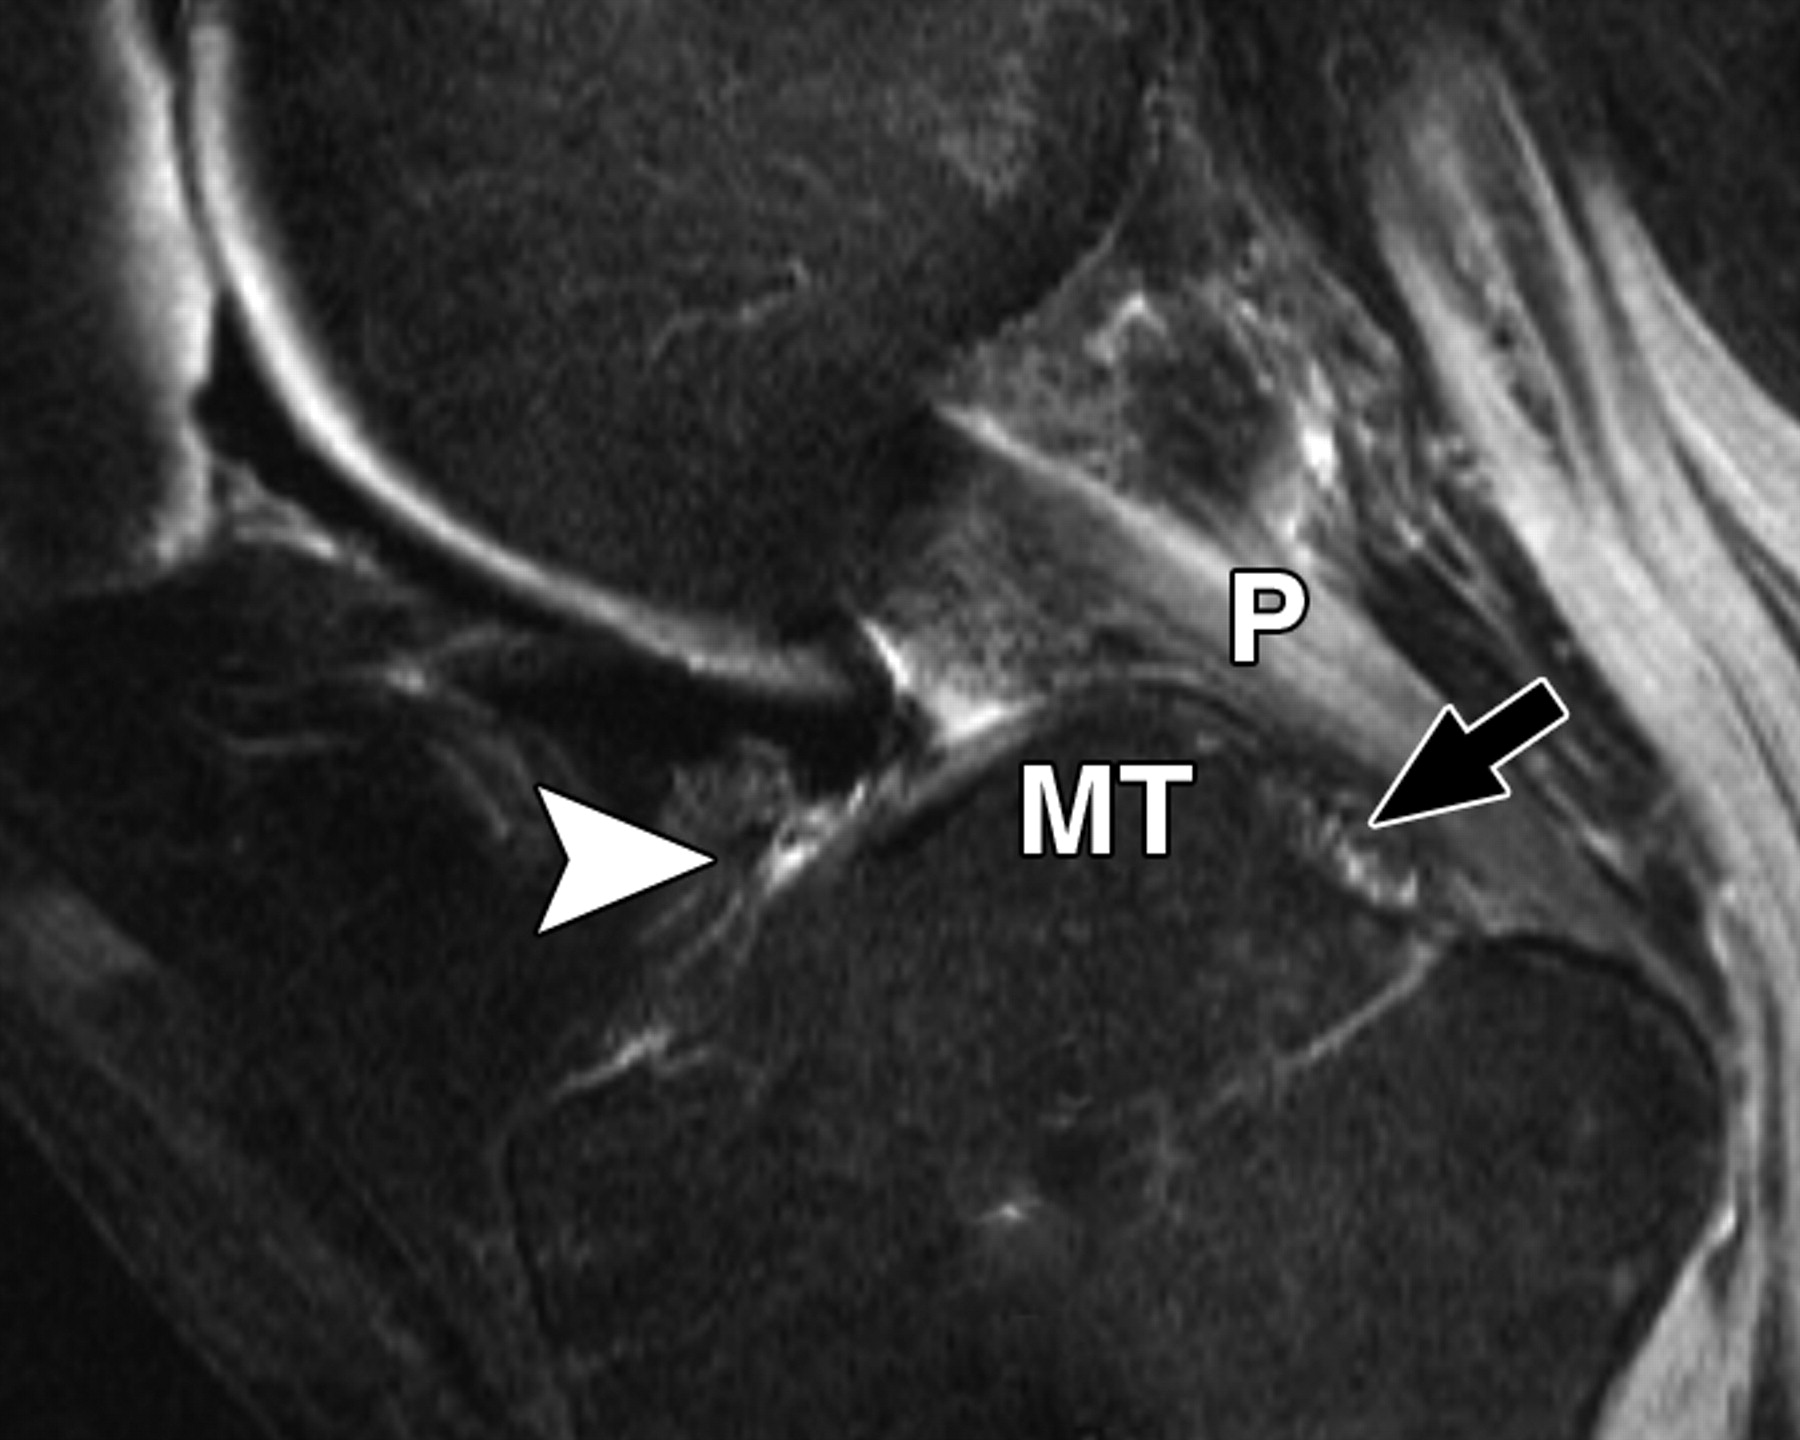

图5D-59岁男性,中等加权、脂肪饱和、涡轮自旋回波(TR/TE eff,3,700/29)3-T MR图像显示半月板后根和交叉韧带的解剖关系。

通过后交叉韧带(P)的矢状图像显示内侧半月板后根的插入部位(箭头)相对于韧带插入部位位于前方。MT =胫骨内侧结节。箭头表示膝前韧带。

图5E-59岁男性,中等加权、脂肪饱和、快速自旋回波(TR/TE,3,700/29)3-T MR图像显示半月板后根和交叉韧带的解剖关系。

通过前交叉韧带(星号)的MRI图像显示外侧半月板后根的附着点(箭头)相对于内侧半月板的附着点稍靠前。圆圈表示前交叉韧带和外侧半月板前根的共同附着点。箭头表示膝前韧带。P =后交叉韧带。